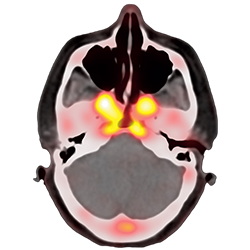

「目指すのは治療の個別最適化です。AIを用いることで、この課題を解決できると考えています。研究では、X線やMRI(磁気共鳴画像)の診断で入手した大量の医療画像をAIに入力し、網羅的に分析を行います。腫瘍の大きさ、丸さ、ギザギザの具合などによって、予後にどのような傾向があるのか定量的に判断できるようになります。技術の進歩により、人間の医師を超える診断能力を持つAIが実現されつつあります。今後はAIと医師が協力して、患者の診断や治療を行う未来がやってくるでしょう」

画像診断の特長は、患部の一部を採取して行う「生検」をしなくて済むこと。患者の負担が少ないだけでなく、脳腫瘍など生検が難しいケースでも利用できる。さらに、血液や呼気を使った検査では難しい、詳細な患部の特定も可能になる。放射線治療の場合、腫瘍のどの部分に放射線を当てるかによって効果が変わることもあるだけに、その有用性は大きい。

「がんの放射線治療の効果がどうなるか予測するバーチャル臨床試験の研究も進んでいます。患者さんから提供を受けた腫瘍の画像をAIに入力すると、どのくらいの期間、どのような放射線治療をすると、どういった効果が得られるかという予測ができます。もちろん、まだまだAIの予測通りになったというエビデンスが足りません。コツコツとデータを集めるのが、研究者としての踏ん張りどころです」